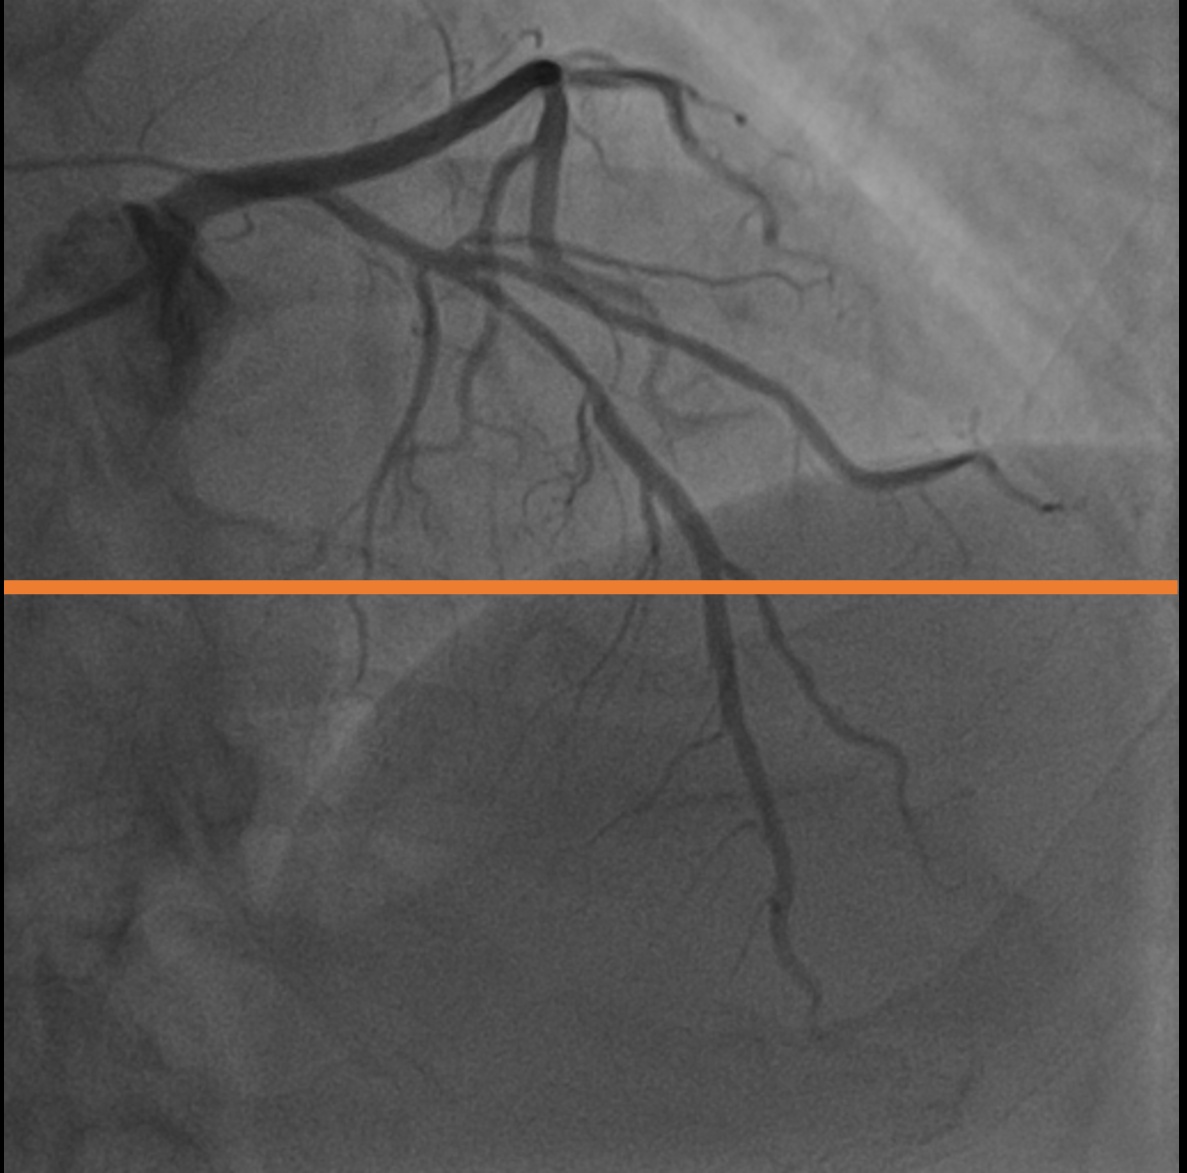

4.1 XACV Dataset

We collect 111 complete records of coronary artery X-ray videos, encompassing the injection, flow through the blood vessels around the heart, and dissipation of the contrast agent. Subsequently, we establish the XACV (X-ray Angiography Coronary Video) dataset. Each video consists of varying numbers of high-resolution coronary artery X-ray images. We invite experienced radiologists to annotate the vascular regions, focusing on one or two frames where the contrast agent is most prominent in each video. The XCAD dataset contains only a single image, and the CADICA video dataset does not provide corresponding ground truth. Therefore, in the following experiments, we conduct all the analyses on our collected XACV dataset and the corresponding GT for each sequence. In Figure 5, we show that compared to other publicly available datasets, XCAD [33] and CADICA [19], our dataset exhibits finer annotations in the vascular regions, providing an advantage for future related tasks. The development and use of our dataset have been approved by our institution’s IRB.